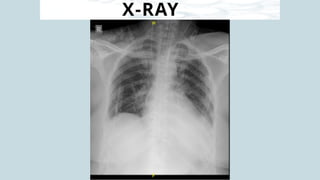

X-RAY